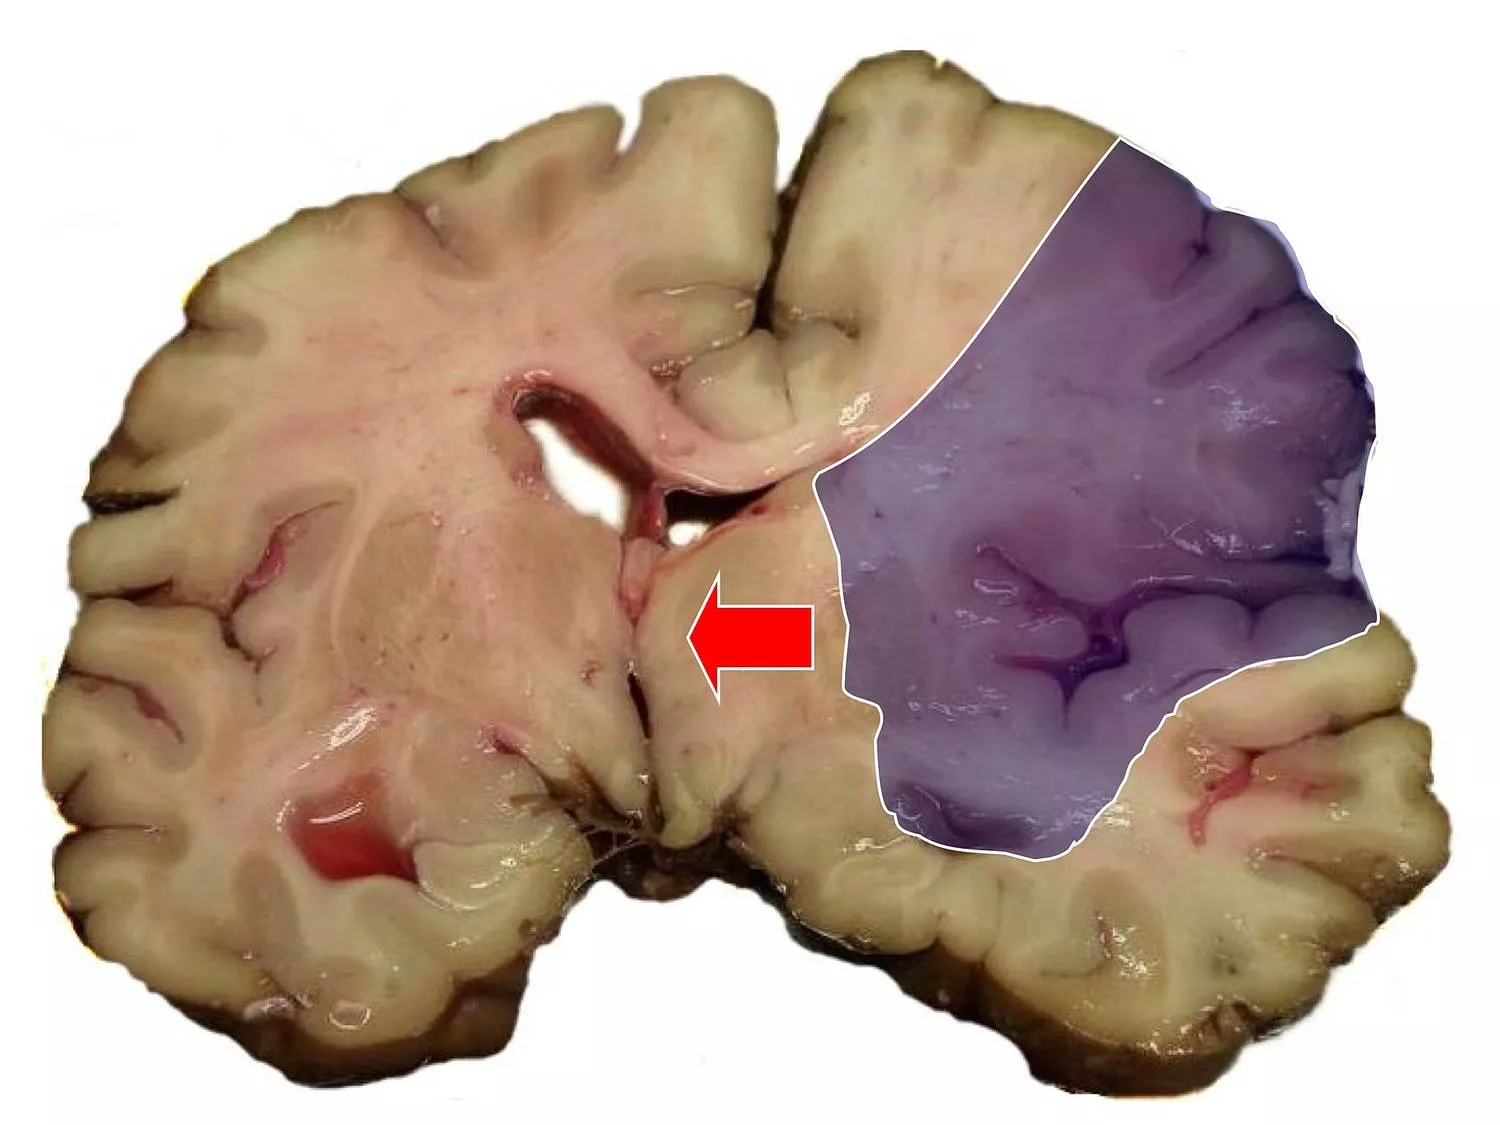

Közleményükben az agyi érkatasztrófát, azaz a sztrókot ismertetve kiemelték, hogy az agy vérellátásában beálló súlyos hiányt az erek megrepedése vagy elzáródása okozza. Ez utóbbit nevezzük iszkémiás sztróknak, ami az esetek túlnyomó részét teszi ki.

A sztrók Európa-szerte a maradandó egészségkárosodás legfőbb oka. A betegség korai szakaszát azonban hosszú, akár hetekig elhúzódó szubakut fázis követi, amely során az agy működése megváltozik, hiszen a szervezet próbál úrrá lenni a sztrók által előidézett káros folyamatokon. Ezt a fázist az orvostudomány egyelőre alig látja át, pedig sokszor ekkor dől el, hogy a páciens maradandó egészségkárosodást szenved, vagy bízhat-e a teljes felépülésben - olvasható a közleményben.

A programban olyan fehérjék szerepét vizsgálják majd, amelyek fő feladata az emberi szervezetben a sejtek közötti fehérjehálózat lazítása, a szövetek vázának karbantartása. Sztrók után azonban ugyanezek a fehérjék az erek gyulladását, az idegsejteket védő vér-agy gát lebomlását idézhetik elő. Agyszövetben felerősödő aktivitásuk nemcsak a sztrók után bekövezett károsodásokat jelzi, hanem hozzájárulhat annak kialakulásához is.